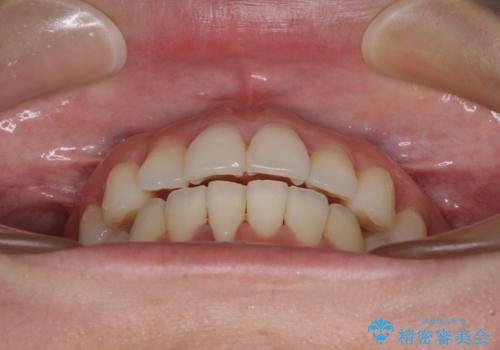

前歯のクロスバイト インビザラインによる矯正治療

- 上下のクロスバイトと前歯のデコボコを気にして来院された患者様です。

インビザラインを用い、IPR(歯と歯の間を削る)と歯列全体を拡大させることで、歯並びを整えていくこととしました。

治療を急いでいらっしゃらなかったため、のんびりと治療を進めていきました。3年以上の期間を要しましたが、きれいな口元に仕上がりました。